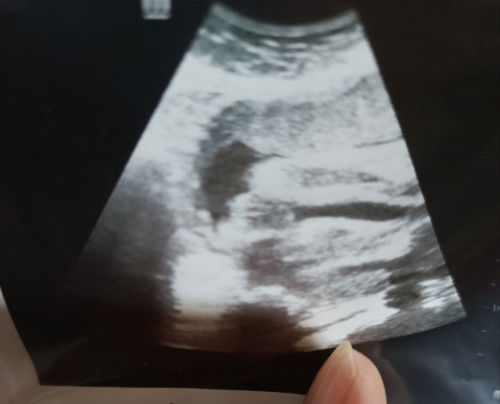

Selamat pagi mommy2 Nak tanya,siapa ada pengalaman scan mcm ni confirm girl ke?

doktor yg scan tu cakap mcm mana?

girl

harap2 betul girl🙏